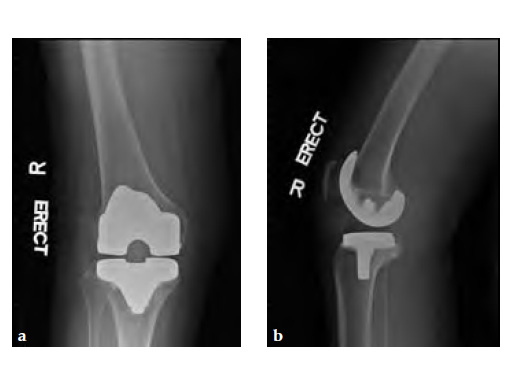

Case 2: A 76-year-old female underwent right total knee replacement 5 years ago and left total knee replacement 4.5 years ago

The patient underwent left L5S1 minimally invasive TLIF with pedicle screws 2 years ago for left lumbar 5th radiculopathy. At the same time she was put on fosamax for osteoporosis.

Case provided by Merng Koon Wong, Singapore, Singapore

Based on the negative MRI thigh and positive MRI lumbar spine of multiple levels of spinal stenosis, the patient underwent epidural analgesic injection. Patient sustained right femur midshaft periprosthetic fracture the next day after her epidural injection with no trauma.